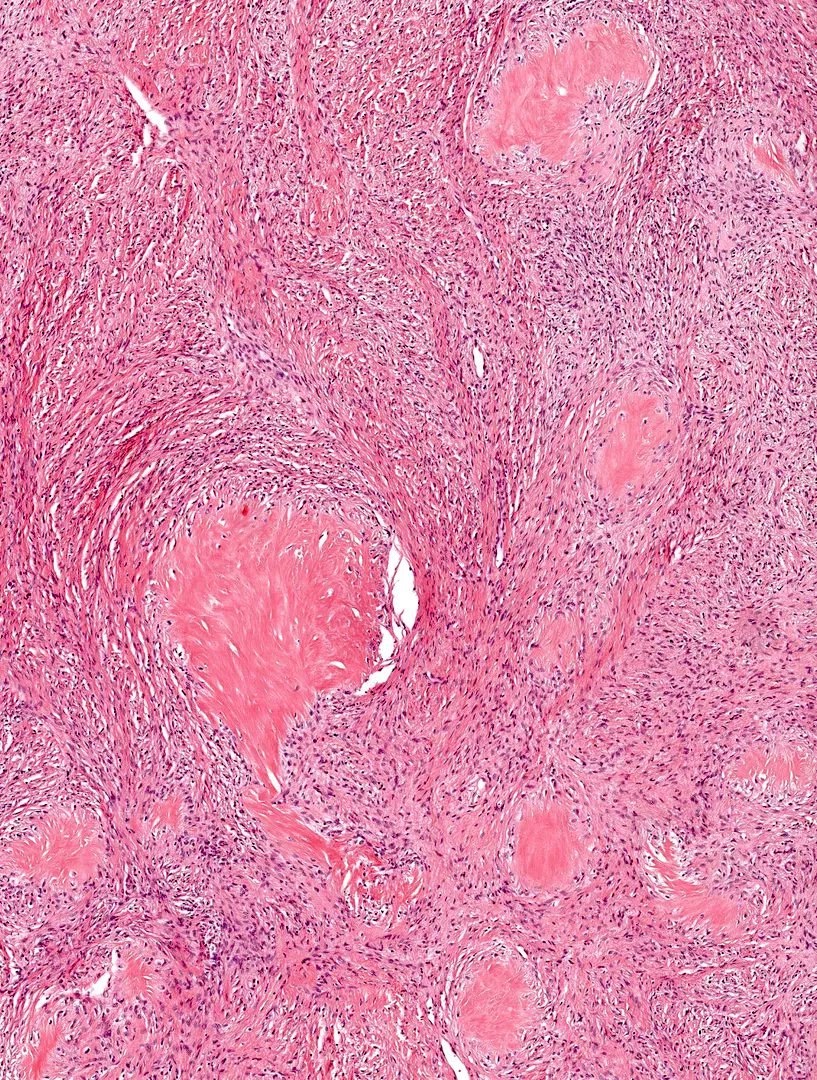

Microscopic (histologic) description

- Low to moderately cellular, bland fusiform or spindled cells with focal to diffuse whirling in heavily collagenized stroma with abrupt transition to myxoid areas

- 45% have epithelioid areas

- 40% contain poorly formed but large collagen rosettes

- Often infiltrates adjacent skeletal muscle

- Occasionally has areas of increased cellularity, atypia, necrosis or mitotic activity characteristic of intermediate to high grade sarcoma

Microscopic (histologic) images